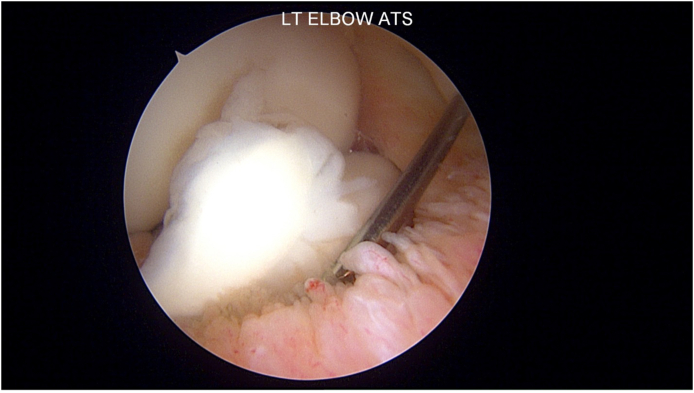

Fig. 2.

Loose body noted in the anterior compartment of a left elbow. The spinal needle can be used to hold it in place in preparation for removal.